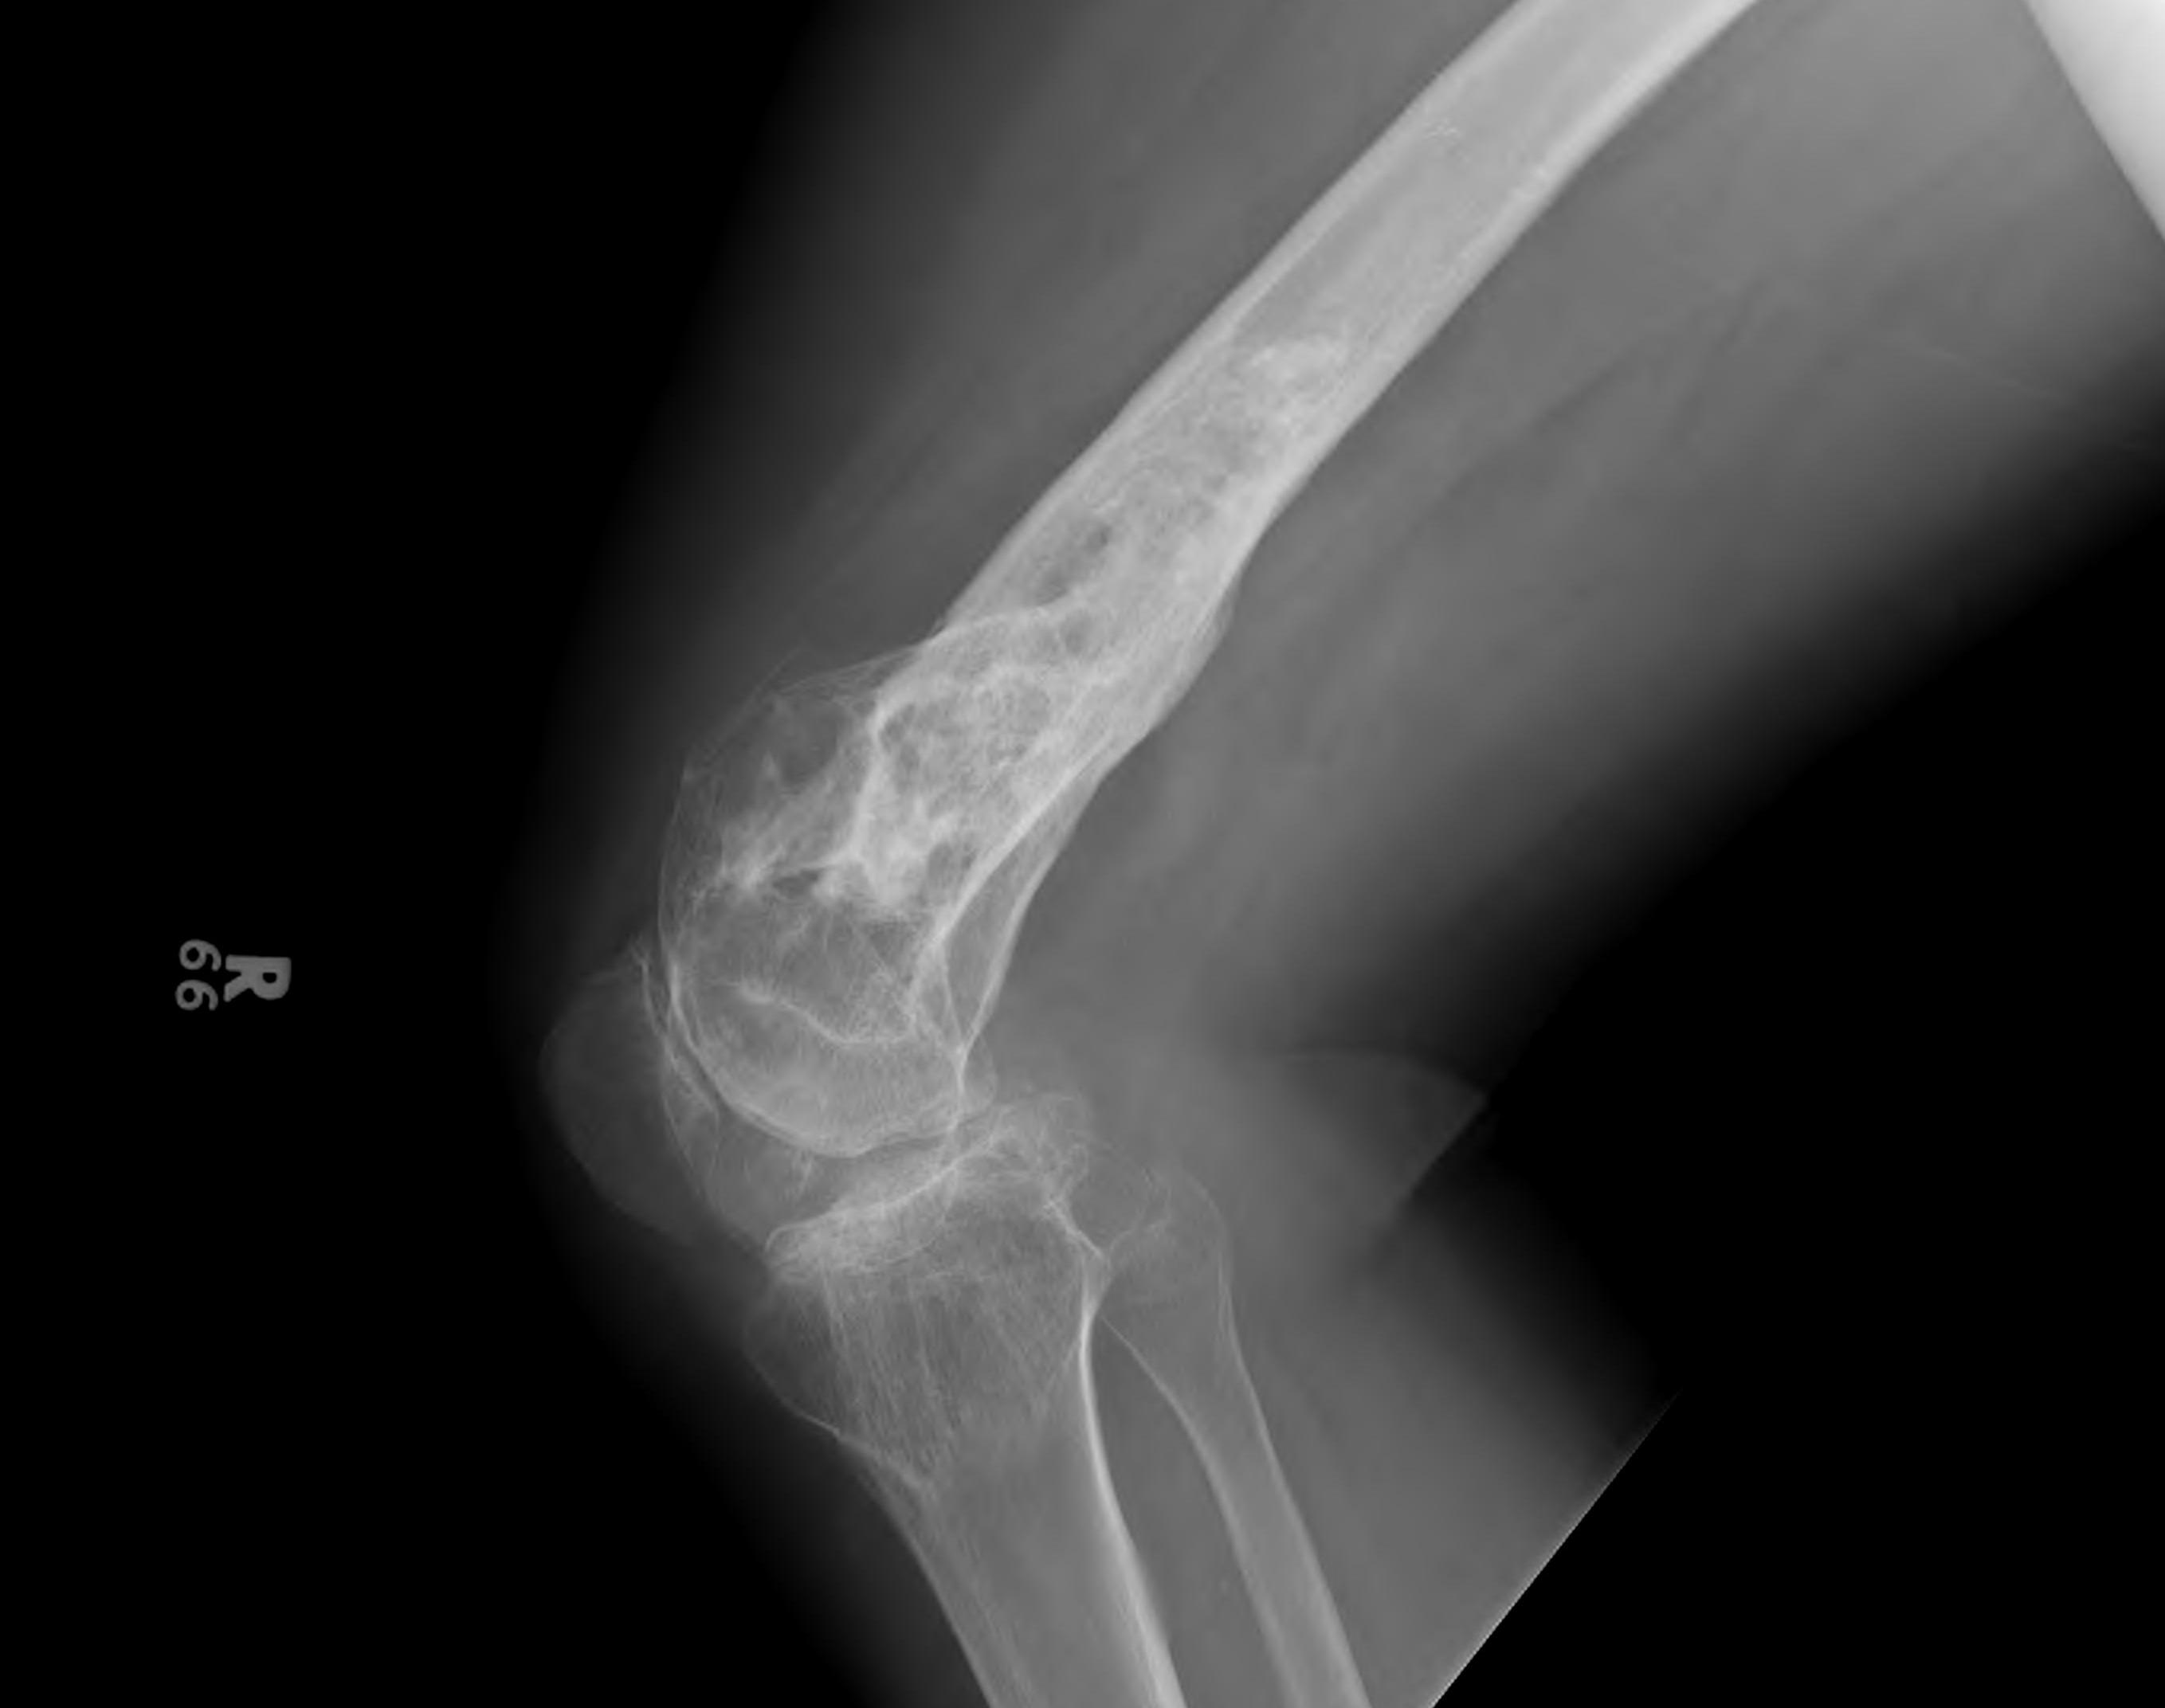

Paget's

Fracture Malunion